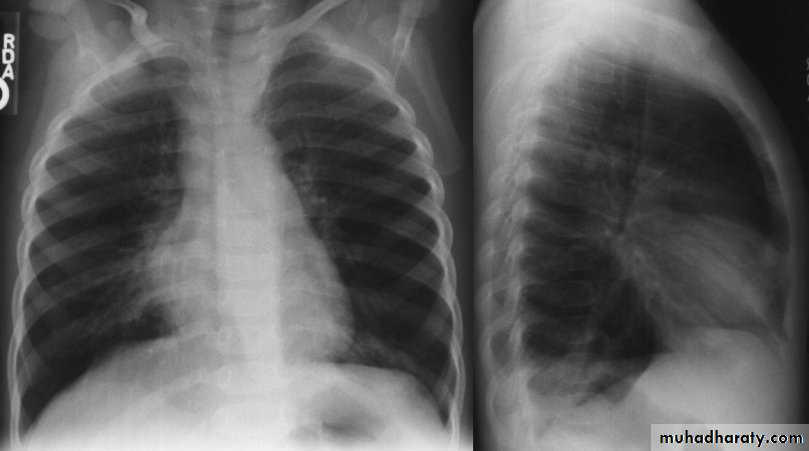

Chest X-ray:

DDx: FB in the esophagus